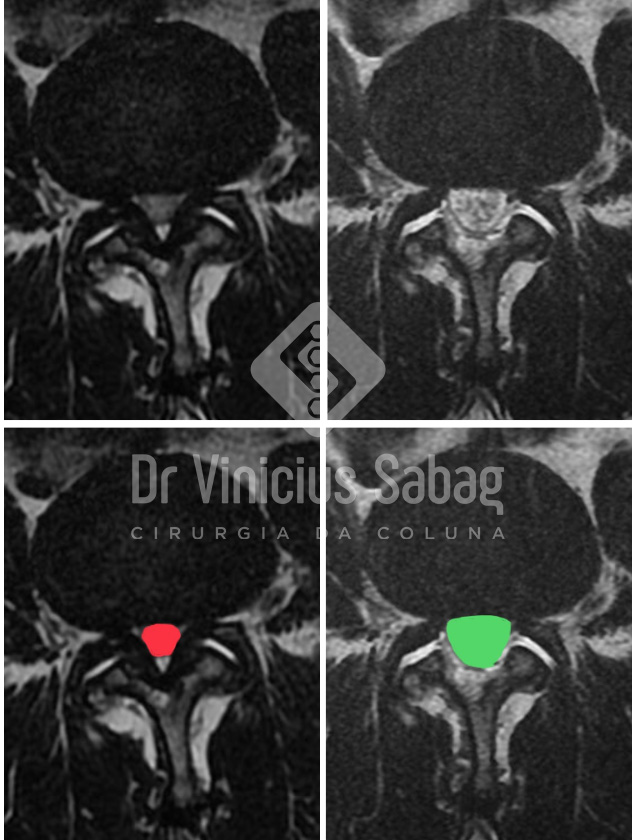

Comparativo entre canal lombar normal (esquerda; seta verde) e canal lombar estreitado/estenose (direita; seta vermelha).

Comparativo entre ressonância pré-operatória (esquerda; vermelho) e pós-operatória (direita; verde) evidenciando descompressão completa do canal lombar.